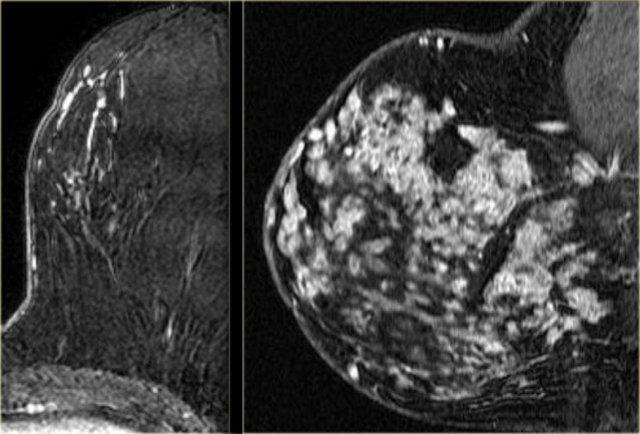

Bên trái là hai ví dụ về ngấm thuốc dạng cụm trong DCIS.

Bên trái là hai trường hợp.

Hình ảnh ngoài cùng bên trái là ung thư ống tuyến xâm lấn biểu hiện dưới dạng khối lớn ngấm thuốc không đồng nhất.

Kế bên là ví dụ về ung thư ống tuyến xâm lấn biểu hiện dưới dạng khối nhỏ hơn với ngấm thuốc dạng viền.